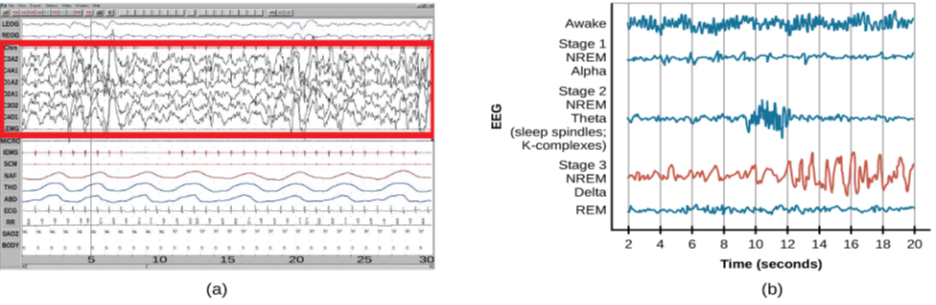

Sleep is not a uniform state of being. Instead, sleep is composed of several different stages that can be differentiated from one another by the patterns of brain wave activity that occur during each stage. These changes in brain wave activity can be visualized using EEG and are distinguished from one another by both the frequency and amplitude of brain waves (Figure 4.7). Sleep can be divided into two different general phases: REM sleep and non-REM (NREM) sleep. Rapid eye movement (REM) sleep is characterized by darting movements of the eyes under closed eyelids. Brain waves during REM sleep appear very similar to brain waves during wakefulness. In contrast, non-REM (NREM) sleep is subdivided into four stages distinguished from each other and from wakefulness by characteristic patterns of brain waves. The first three stages of sleep are NREM sleep, while the fourth and final stage of sleep is REM sleep. In this section, we will discuss each of these stages of sleep and their associated patterns of brain wave activity.

The first stage of NREM sleep is known as stage 1 sleep. Stage 1 sleep is a transitional phase that occurs between wakefulness and sleep, the period during which we drift off to sleep. During this time, there is a slowdown in both the rates of respiration and heartbeat. In addition, stage 1 sleep involves a marked decrease in both overall muscle tension and core body temperature.

In terms of brain wave activity, stage 1 sleep is associated with both alpha and theta waves. The early portion of stage 1 sleep produces alpha waves, which are relatively low frequency (8–13Hz), high amplitude patterns of electrical activity (waves) that become synchronized (Figure 4.8). This pattern of brain wave activity resembles that of someone who is very relaxed, yet awake. As an individual continues through stage 1 sleep, there is an increase in theta wave activity. Theta waves are even lower frequency (4–7 Hz), higher amplitude brain waves than alpha waves. It is relatively easy to wake someone from stage 1 sleep; in fact, people often report that they have not been asleep if they are awoken during stage 1 sleep.

As mentioned earlier, REM sleep is marked by rapid movements of the eyes. The brain waves associated with this stage of sleep are very similar to those observed when a person is awake, as shown in Figure 4.11, and this is the period of sleep in which dreaming occurs. It is also associated with paralysis of muscle systems in the body with the exception of those that make circulation and respiration possible. Therefore, no movement of voluntary muscles occurs during REM sleep in a normal individual; REM sleep is often referred to as paradoxical sleep because of this combination of high brain activity and lack of muscle tone. Like NREM sleep, REM has been implicated in various aspects of learning and memory (Wagner, Gais, & Born, 2001; Siegel, 2001).

The different stages of sleep are characterized by the patterns of brain waves associated with each stage. As a person transitions from being awake to falling asleep, alpha waves are replaced by theta waves. Sleep spindles and K-complexes emerge in stage 2 sleep. Stage 3 and stage 4 are described as slow-wave sleep that is marked by a predominance of delta waves. REM sleep involves rapid movements of the eyes, paralysis of voluntary muscles, and dreaming. Both NREM and REM sleep appear to play important roles in learning and memory. Dreams may represent life events that are important to the dreamer. Alternatively, dreaming may represent a state of protoconsciousness, or a virtual reality, in the mind that helps a person during consciousness.